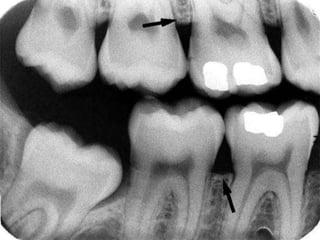

ENAMEL -outermost

radioopaque layer of the

crown of tooth.

DENTIN-Radioopaque but less

than enamel

Found beneath enamel layer

and surrounds pulp cavity.it

comprises most of the tooth

CEMENTUM-Usually not

apparent radiographically

because the contrast between it

and dentin is low and also

because it is a very thin layer

PULP CHAMBER- it consists of

pulp chamber and root canal.it

appears radiolucent.

RESTORATIVE MATERIALS

 Amalgam-completely

radioopaque

 Gold-radioopaque

 Stainless steel pins-highly

 Composite rest.-radiolucent

over radioopaque metal

coping.